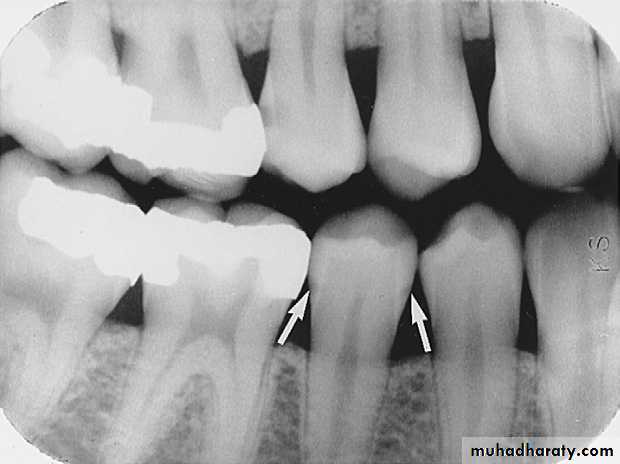

Advanced lesion identified by arrows.

An advanced carious lesion, which extends through the dentino-enamel junction (DEJ) and into dentin, seen on the distal surface of the mandibular first molar.

Advanced Interproximal Caries

extends to or through the DEJ and into dentin but does not extend through dentin more than half the distance toward the pulpAdvanced Interproximal Caries

Interproximal Caries (Advanced)